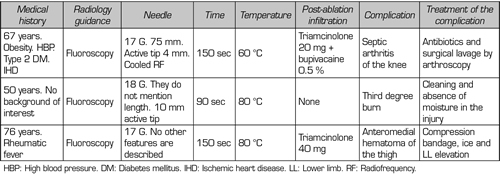

Complications and side effects of TRF of genicular nerves

In our review, we found no patient who presented persistent weakness or neuralgia after TRFGN (15,25,26). We found published a case of a third degree burn on the area where the IMGN was located (29) and another case of septic arthritis of the knee after performing this interventional technique (30) (Table V).

Table V. Complications and side effects of TRF of genicular nerves

In our review, we found no patient who presented persistent weakness or neuralgia after TRFGN (15,25,26). We found published a case of a third degree burn on the area where the IMGN was located (29) and another case of septic arthritis of the knee after performing this interventional technique (30) (Table V).

Kim (31) reviewed the vascular complications of the genicular arteries described in the surgical literature. The most frequent complication was the formation of pseudoaneurysms (mainly after open synovectomies, menisectomies, arthroscopies, and total knee arthroplasties), other complications found were arteriovenous fistulas, hemarthrosis, and osteonecrosis of the patella. Fortunately, these surgical complications are not described after TRFGN, but it does not mean that there is no risk of vascular injury. In fact, a clinical case of a hematoma that was treated conservatively after an TRFGN was described (32).